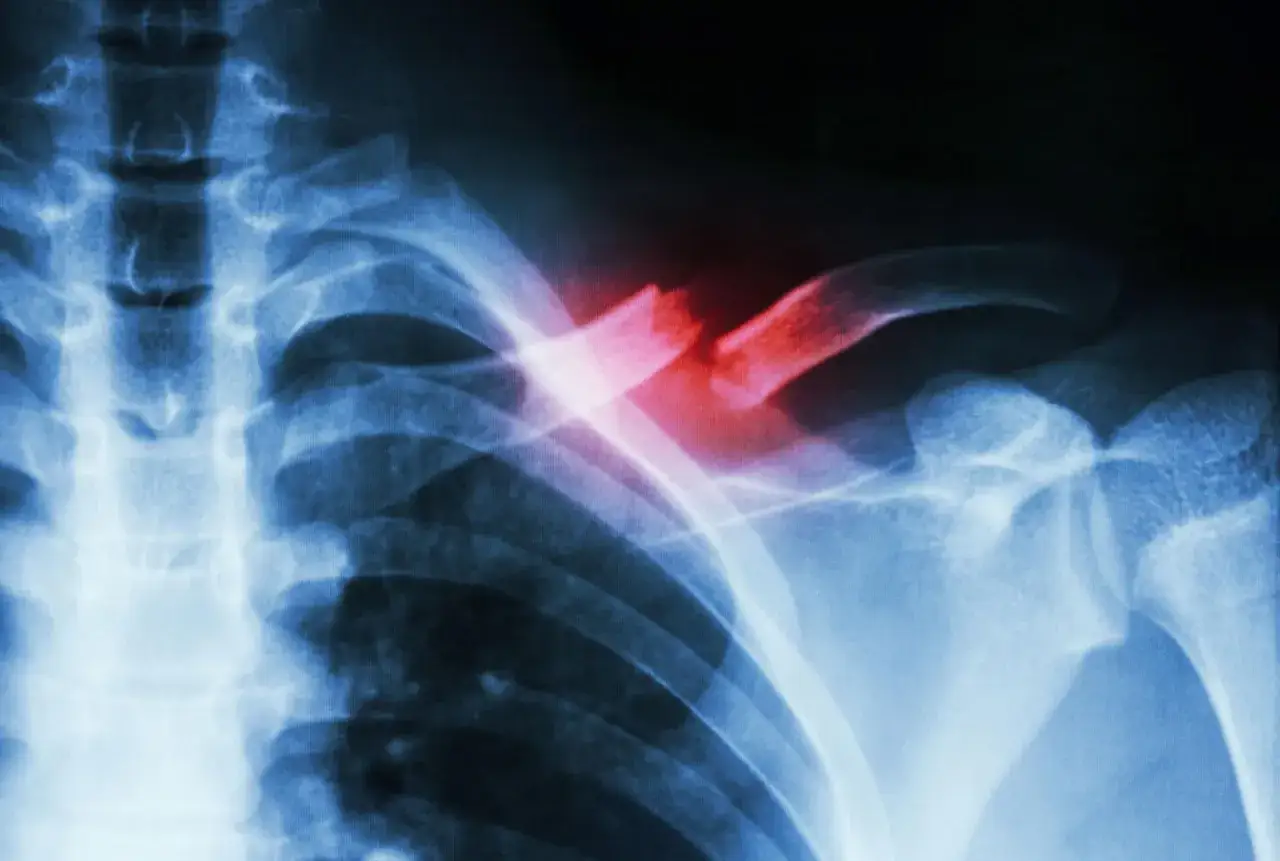

Kluczowym elementem diagnozy jest badanie obrazowe. RTG to podstawowe narzędzie, które pozwala potwierdzić złamanie i określić jego rodzaj. W niektórych przypadkach mogą być potrzebne dodatkowe badania, takie jak USG czy tomografia komputerowa.

RTG to podstawowe badanie w diagnostyce złamanego obojczyka u dziecka. Zdjęcie rentgenowskie pozwala dokładnie ocenić rodzaj złamania, jego lokalizację i ewentualne przemieszczenie odłamków kostnych. To kluczowe informacje dla planowania leczenia.

W niektórych przypadkach lekarz może zalecić USG, które jest szczególnie przydatne u małych dzieci. Tomografia komputerowa jest rzadko stosowana, głównie przy skomplikowanych złamaniach lub podejrzeniu dodatkowych urazów.

Operacja jest konieczna w przypadku złamań z dużym przemieszczeniem odłamków, otwartych złamań lub gdy występuje ryzyko uszkodzenia naczyń krwionośnych czy nerwów. Zabieg polega na odpowiednim ustawieniu odłamków kostnych i ich stabilizacji za pomocą specjalnych płytek lub śrub.